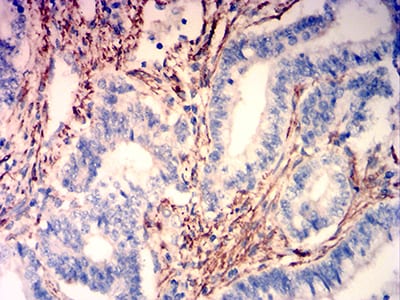

分类: 科研抗体货号: 31764别名: CDM; HCAD; LCAD; H-CAD; L-CAD; NAG22应用: WB,IHC,FCM反应种属: Human, Mouse, Rat